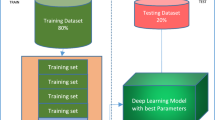

COVID-19 has affected more than 520 million population worldwide by April 2022. Few medical examinations such as rapid antigen and RT-PCR are recommended for timely diagnosis of COVID-19. However, RT-PCR and other similar type of tests can show the presence of virus only within eight to thirteen days. Furthermore, the chest related complications that arise as a result of COVID-19 (such as pneumonia and Acute Respiratory Distress Syndrome (ARDS)) cannot be diagnosed through these tests. In the present article, we have proposed a deep Convolutional Neural Network (CNN) based model, named \(\mathrm SRC_{2}\) that can differentiate between a normal and COVID-19 affected Chest X-Ray image. The proposed model consists of two modules, \(\mathrm SRC_{2}\)F and \(\mathrm SRC_{2}\)C for feature extraction and classification respectively. We have done feature extraction using existing trained CNN models and our proposed model \(\mathrm SRC_{2}\)F. Then, we have implemented standard classifiers and our proposed classifier \(\mathrm SRC_{2}\)C over the extracted features. Finally, we have compared the performance of our proposed Feature extractor module and classification module. Experimental results show that our proposed model \(\mathrm SRC_{2}\) has obtained an accuracy of 98.68 percent which is better than the existing methods.